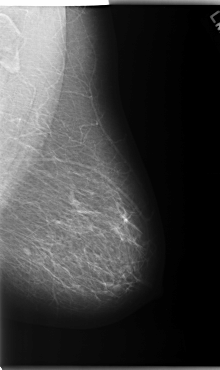

C_0174_1.RIGHT_MLO

C_0174_1.RIGHT_CC

RIGHT_CC LINES 5912 PIXELS_PER_LINE 3672 BITS_PER_PIXEL 12 RESOLUTION 50 OVERLAY

RIGHT_MLO LINES 5856 PIXELS_PER_LINE 3744 BITS_PER_PIXEL 12 RESOLUTION 50 OVERLAY